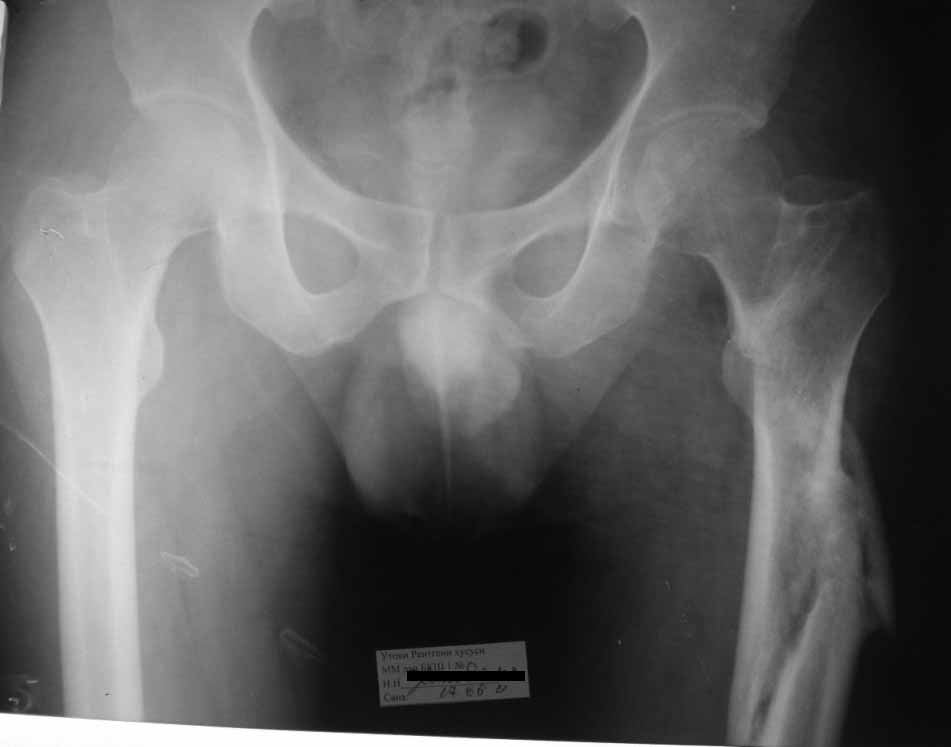

Уважаемые коллеги, доброго времени суток. Молодой парень 30 лет, в 2010г получил травму в результате ДТП. Лечили на скелетном вытяжени 6 нед с последующим наложением кокситной повязки на 12 нед. От предложенного остеосинтеза пластинами воздержался( БИОС к сожалению пока не доступен)В настоящее время ходит заметно прихрамывая, левая нижняя конечность укорочена сравнительно на 3,0 см. Объем движений в суставах полный. Как можно помочь больному в дальнейшем. Буду рад Вашим советам. Спасибо.

Здравствуйте Шухрат. Мне кажется, если хромата в результате укорочения конечности,а не из-за других причин, то оптимально будет произвести остеотомию в с/з и установить аппарат Илизарова.

Согласен с Вами, мое мнение нужно востоновить длину. В наших условиях это остеотомия и остеосинтез пластиной с учётом риска и осложнений, или же ему нужно будет оперироватся там где БИОС имеется.Был бы рад советам по поводу моего мнения.